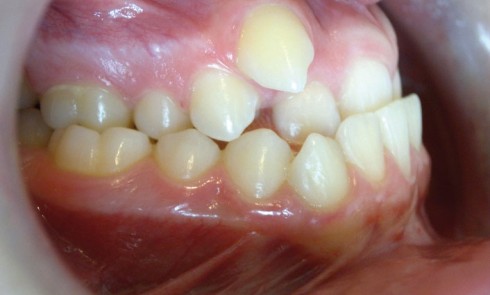

Article réservé à nos abonnés Classe III en fin de croissance

Rappel de la problématiqueGuillaume, 14 ans, se présente pour la première fois en consultation d’orthodontie, adressé par son dentiste. Il...